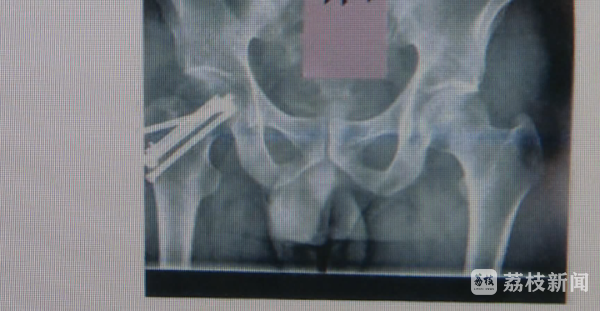

当时,李先生在小区物业处报名参加了亲子趣味运动会。活动当天的场地为某小学的室内篮球场,参与人数有100多人,活动共有6个项目:垃圾分类我知道、踩气球、夺“宝”骑“兵”、并驾齐驱等,吕先生在进行第4项“并驾齐驱”时倒地受伤,造成右股骨颈骨折。经过医院手术治疗后,司法鉴定部门认定吕先生所受伤害构成十级残疾。吕先生表示,社区和某天下中心作为亲子活动的组织者,明知活动过程中有摔倒风险,还将活动场地由草坪地面的操场改为水泥地板的室内篮球场,且未对室内篮球场做任何的防护装置。在进行风险比较大的项目时,工作人员没有告知参加人员活动的规则及注意事项,仅由一组家庭做个示范即开始比赛,活动现场一片混乱,组织方未尽到安全保护义务。